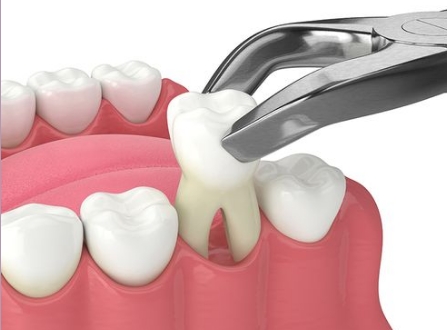

Det kan være flere årsaker til at en tann må fjernes. På grunnlag av en klinisk undersøkelse og røntgenbilder, kan tannlegen vurderer om tannen kan trekkes på vanlig måte, eller om den må opereres ut. Inngrepet skjer i begge tilfeller under lokalbedøvelse. Dersom tannen må opereres ut, vil man brette tannkjøttet til side, fjerne nødvendig kjeveben og dele tannen opp etter behov. Behandlingen avsluttes ved at såret renses og det settes et nødvendig antall sting.

Etter inngrepet:

Når bedøvelsen går ut (etter 3-4 timer), vil det bli noe smerter i området. Du vil derfor få smerte-stillende tabletter eller resept på smertestillende tabletter med deg. Det er anbefalt å ta det med ro de første dagene etter at tannen er fjernet. Unngå derfor hardt fysisk arbeid, trening o.l. i denne perioden. Det kan også forekomme hevelse og gapevansker i noen døgn etter inngrepet.